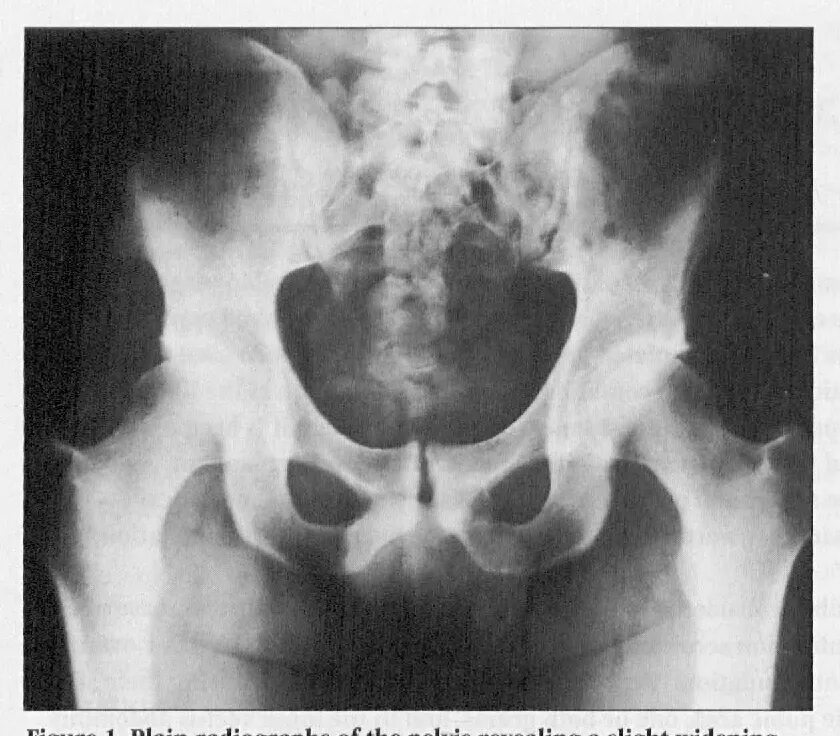

Лонное сочленение что это